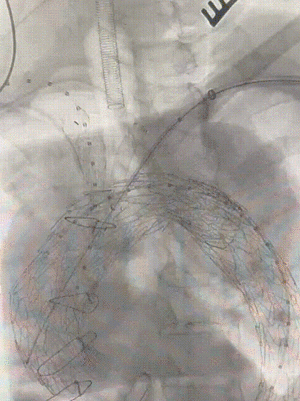

3. LCCA重建:扩充预置在右颈总的PTA球囊为脑部提供血流,吸引器沿短鞘置入左颈总后经左、右前斜确认后出针破膜,用6mm、8mm高压球囊逐级扩张后,置入VIBAHN VBHR080502W。

左颈总破膜出针

左颈总覆膜支架释放并后扩

4. IA重建:左颈总置入穿刺针顶紧覆膜支架后经左、右前斜确认后出针破膜,用6mm、8、12mm高压球囊逐级扩张后,置入HGB161407。

右颈总破膜出针